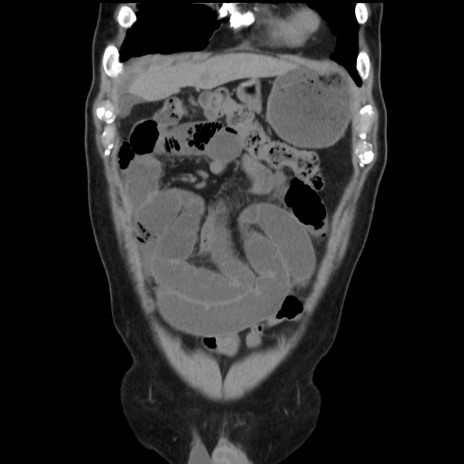

症例16(冠状断像)

【症例】 70歳代男性

【主訴】 腹痛、嘔吐

【現病歴】 約1ヶ月前より間欠的に腹痛と嘔吐あり、当院消化器内科を受診したところCTで多発する肝臓のLDAを指摘され、精査中であった。以降は消化器症状は安定していたが、2日前より嘔気と腹痛があり、同日より排便・排ガスが消失した。改善認めず、 本日、救急外来を受診した。

【既往歴】 大腸ポリープ切除後。

【身体所見】意識清明・会話良好、BT 36.3℃、BP 127/80mmHg、 P 80bpm、腹部:膨満あり、平坦・軟、上腹部正中および下腹部正中に圧痛あり、反跳痛なし、筋性防御なし。

【データ】WBC 7200、CRP 0.77